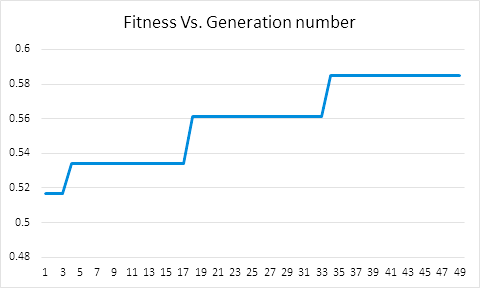

For finding optimal projections based on micro-DE (4 out of 180), we set the parameters of micro-DE to be NFC, , , , and we run each experiment 30 times. For optimal projections based on micro-DE (8 out of 180), we set NFC, , , , and we run each experiment 30 times. The results are presented in Tables 2, 3 and 4. In all cases, micro-DE (MDE) with 4/180 reaches the same correlations as brute force (BF) for 4/16. Of course, MDE finds different projections as it is searching the entire search space of . However, that the same level of reconstruction accuracy can be achieved establishes the reliability of MDE as a practical solution that may even produce a higher-level of uniqueness for Radon barcodes as 4 projections are selected among all 180 angles (the increased uniqueness needs to be verified by applying the Radon barcodes for image retrieval). On the other hand, MDE for 8/180 clearly increases the correlation with statistical significance. This is very encouraging as we can generate more expressive Radon barcodes using a higher number of projections.

Table 5 show the average correlation (accuracy) of brute force versus micro-DE for all 10 image classes. As it can be observed micro-DE can find optimal angles for 4/180 case with statistically the same correlation as for brute force in case of 4/16. Further, micro-DE can achieve higher accuracies in case we configure it for 8/180. We run experiments in Matlab (R2015a) on a Windows 8 machine (LENEVO, Intel i7, 2.6GHz with 8GB memory). The brute force approach (4/16) took on average 16.51 seconds fro each image. Micro-DE needed 8.23 seconds for 4/16, 10.90 seconds for 4/180, and 16.28 seconds for 8/180.